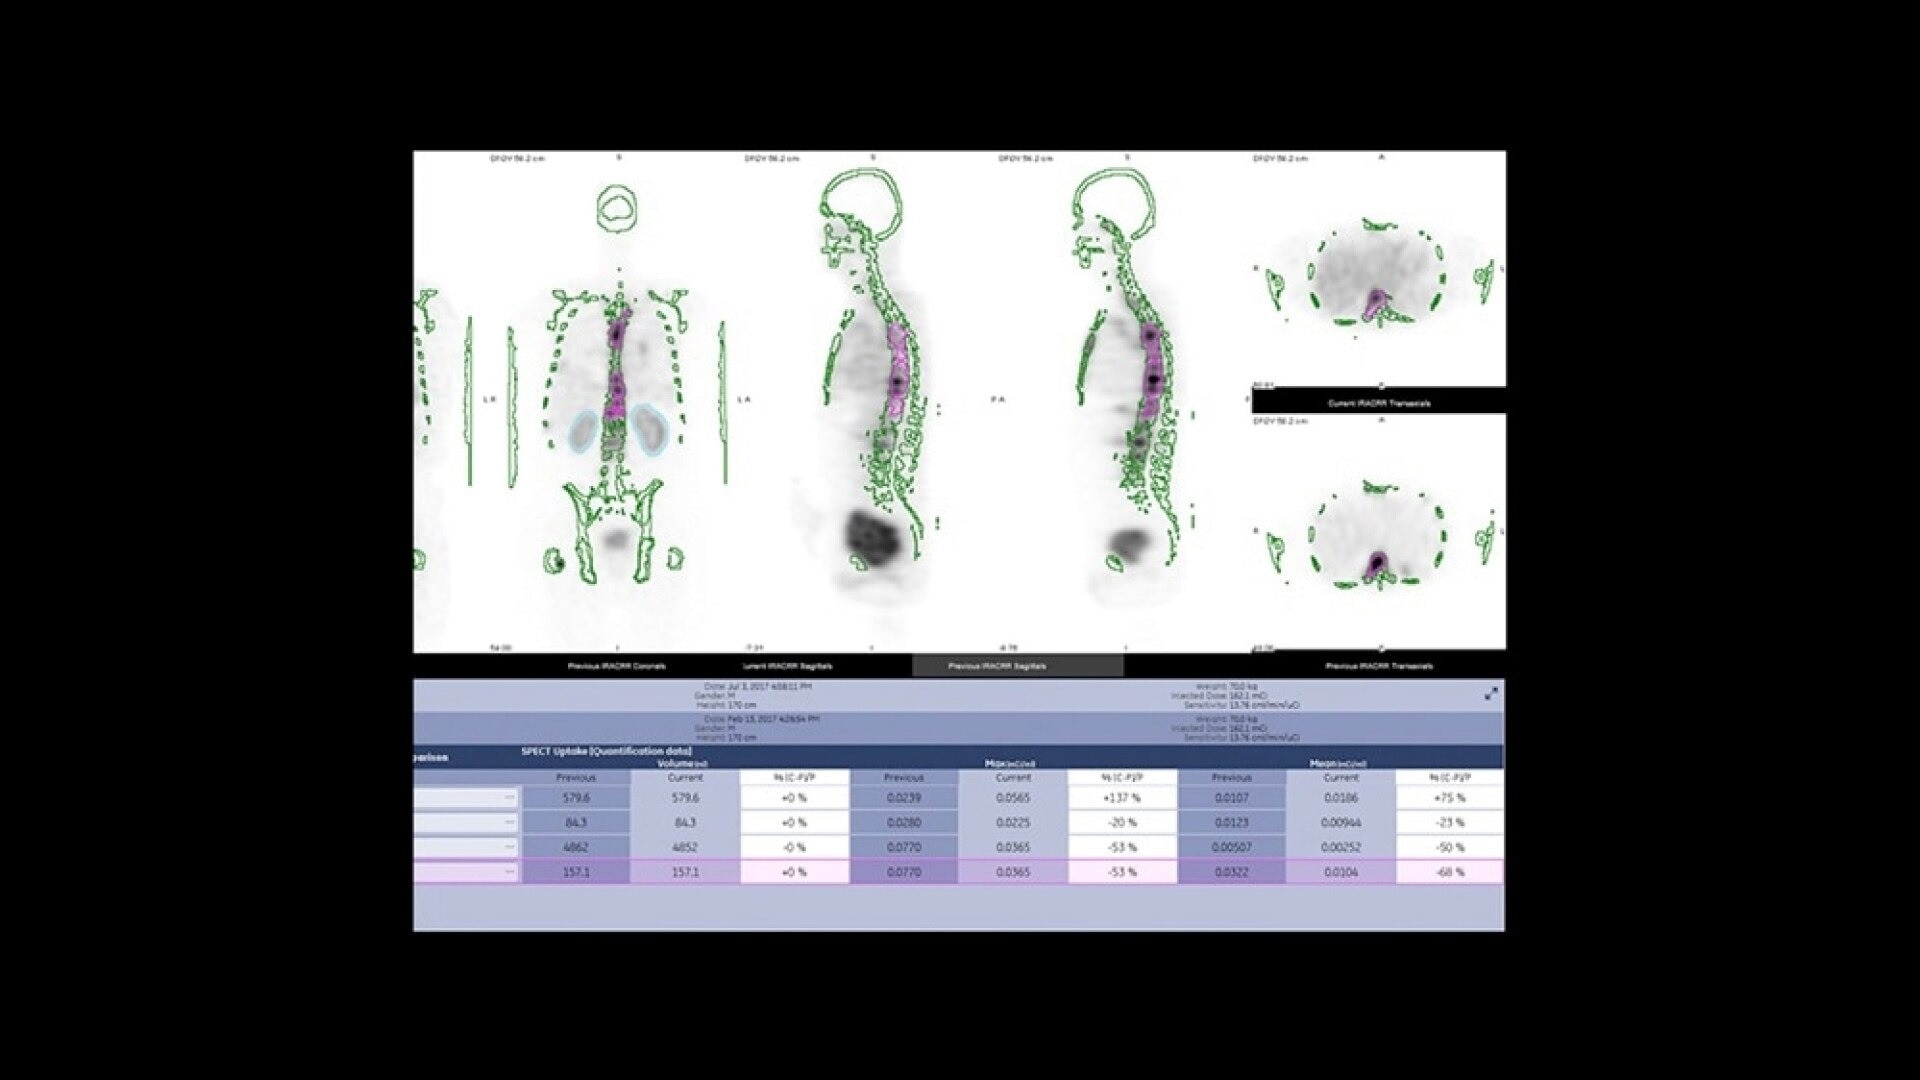

Quantitative SPECT/CT for every patient, every day

NM/CT 870 CZT is a SPECT/CT built for consistent, reproducible quantitation. Improvements to detector performance enable exceptional spatial and energy resolution. It also leverages CT-based attenuation and scatter correction along with Evolution3 image reconstruction. In addition, ever-increasing computational power enables precise camera calibration for less variation between exams.

Once your quantitative studies are acquired, SmartConsole - together with Xeleris - makes it easier to access them. Your quantitative SPECT/CT studies are automatically transferred directly to the PACS or other pre-defined DICOM destinations. An additional dataset in PET DICOM format allows you to review and evaluate images on the same devices you use to view your PET/CT studies, as adjacent information to the original SPECT/CT images.

One home for all your molecular images

SmartConsole makes advanced procedures more accessible by transferring exams directly to the PACS or other pre-defined DICOM destinations with no operator intervention, even if SPECT/CT fusion is not supported, by exporting the studies in DICOM PET format. You can generate and send an additional dataset in PET DICOM format to enable quantitative SPECT results and SPECT SUV (Standard Uptake Value) on any PET DICOM compliant workstation or PACS. Referring physicians can review and evaluate your SPECT/CT exams with the same quality of information they have come to expect from your PET/CT, as adjunct information to the original SPECT/CT images.